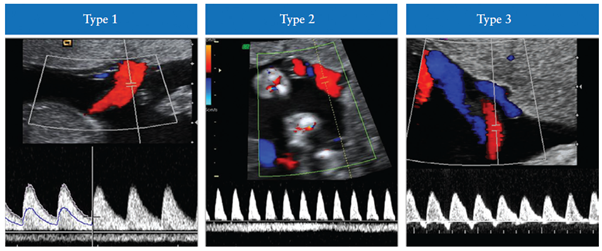

selective FGR (sFGR)의 정의는 EFW가 10퍼센타일 미만이고 두 태아간 EFW의 불일치가 25%를 초과할 때로 정의한다. 이융모막의 경우 2주마다, 단일융모막의 경우 매 1주마다 도플러 검사를 시행하도록 권고한다(그림 3). 일측태아사망이 예상되는 경우 임신 26주 이전에 selective termination을 고려한다.

그림 3. 단일융모막 쌍태임신에서 selective FGR (sFGR)의 분류.

Type I, the umbilical artery Doppler waveform has positive end-diastolic flow

Type II, there is absent or reversed end-diastolic flow (AREDF)

Type III there is a cyclical/intermittent pattern of AREDF.